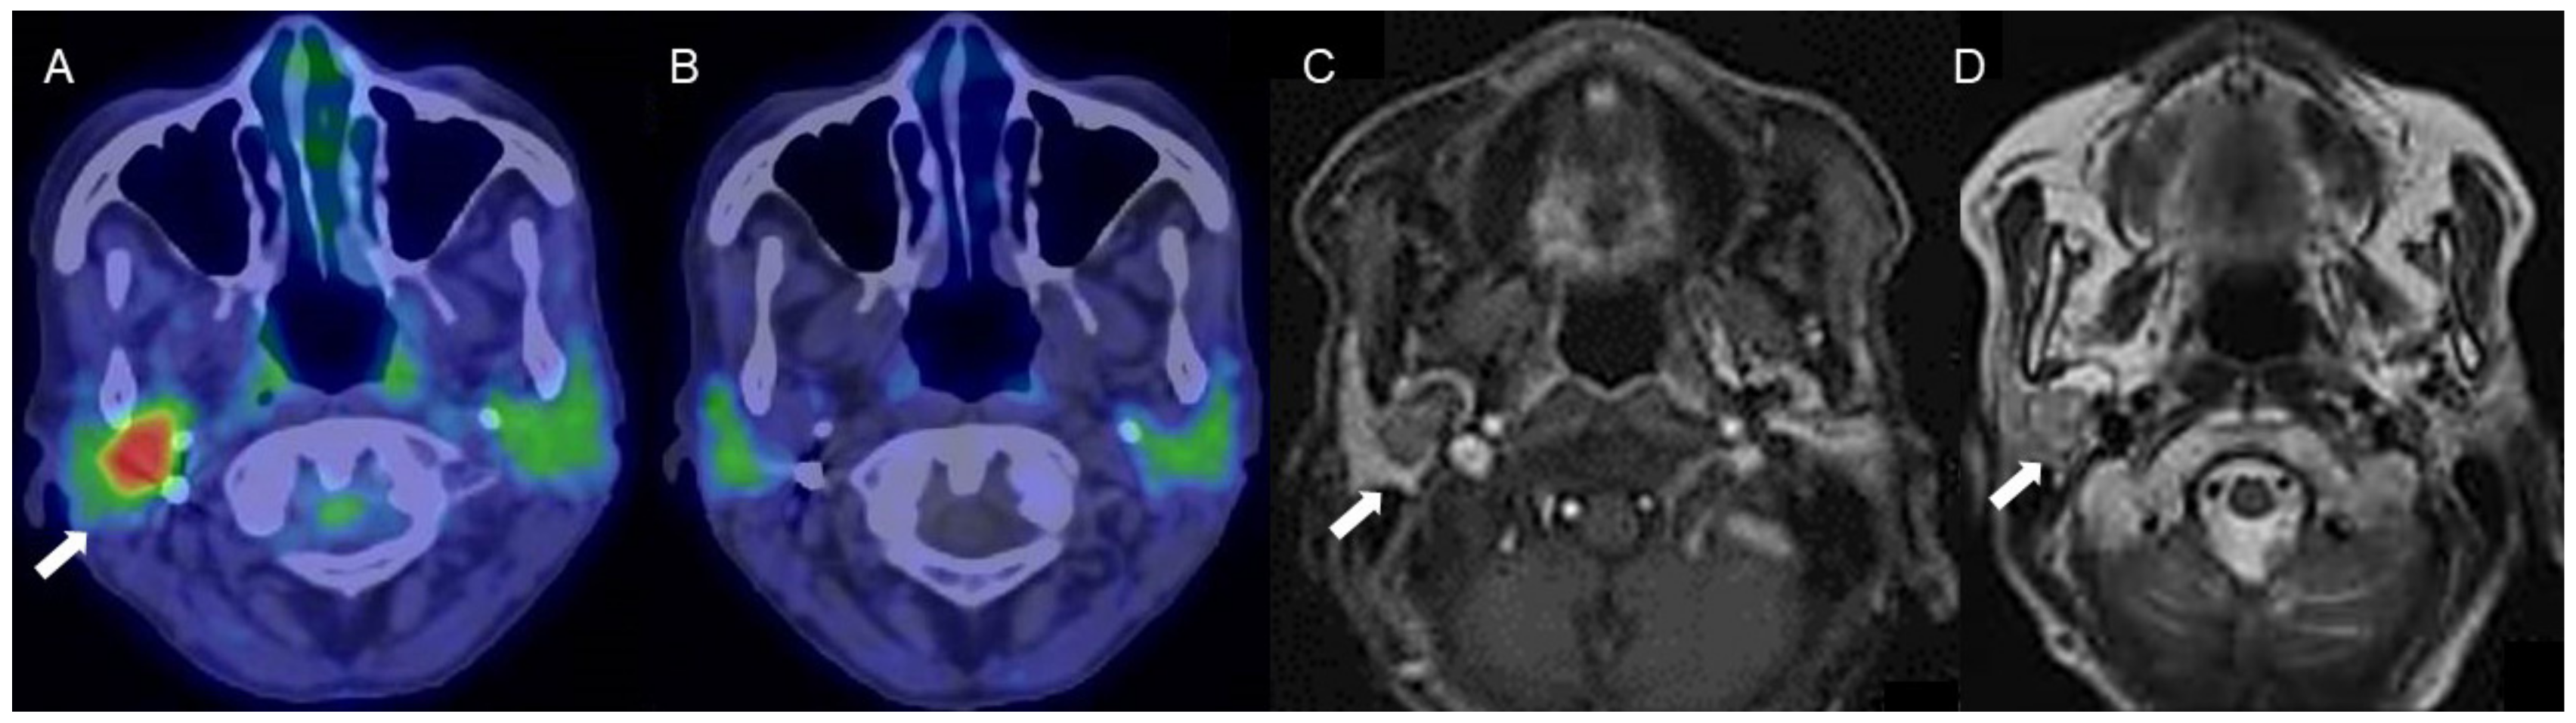

Figure 3.

A woman in her 70s with a tumor of the right parotid gland, highly suspected to be pleomorphic adenoma (arrows). (A) Fused FDG-PET/CT image (axial view), (B) fused 4DST PET/CT image (axial view), (C) Gd-enhanced MRI (axial view), and (D) T2WI MRI image (axial view). On T2WI, a well-circumscribed intraparotid mass of intermediate-to-high signal and a low-signal rim is seen, with heterogeneous nodular enhancement, characteristic of pleomorphic adenoma [20]. The tumor shows increased FDG uptake (SUVmax: 5.2) but no 4DST uptake.